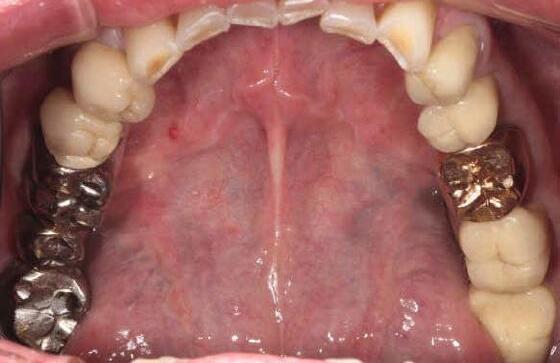

Why deep margin elevation?

Deep margin elevation will make the impression easier by moving the proximal margin of the restoration supra-gingivally, which is especially important for intra-oral scanning. It helps in avoiding periodontal surgical procedures. It makes isolation of the prepared tooth and luting of the final restoration easier.

Tips and Tricks

• Isolation with rubber dam is highly recommended.

• For a better emergence profile, use Teflon tape in the space between the matrix and the adjacent tooth instead of a wedge. Do not use the same matrix as you use for creating a contact point in direct restorations.

• Selective etching of the enamel is recommended.

• Use XBW shade of G-aenial® Universal Injectable for easy differentiation between the tooth, composite material and the restoration.

• The height of the new margin should be slightly above the gingival margin (1mm).

any overhangs. Expose the enamel

1. Clean the tooth surfaces, rinse thoroughly and dry.

2. Apply a matrix adapted to the technique. Gingival margin of the preparation should be well sealed.

3. Etch the enamel.

5. Dry and light-cure.

6. Apply G-ænial Universal Injectable to the gingival margin of the proximal box.

7. Light cure

8. Remove the matrix and check for

covered with adhesive on the rest of the tooth with a fine grit diamond bur.

4. Apply a bonding agent (G-Premio BOND or G2-BOND Universal).